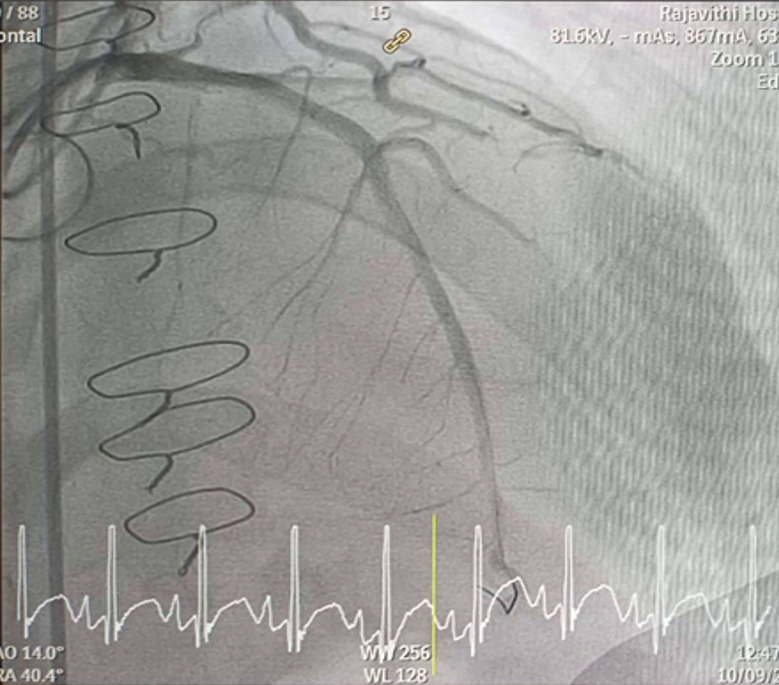

Inserted Sion wire and thrombuster to LAD revealed multiple red clots.SC balloon 2.0 x 15 mm, then 2.5 x 15 mm, was inflated at mLAD up to 12 atm. IVUS insertion to LAD revealed vessels’ size LM 5-5.5 mm, pLAD 4-4.5 mm, mLAD 3-3.5 mm with intraluminal thrombus, dLAD 2.75-3 mm. Multiple inflations were done at mLAD with SC balloon 2.5 x 15 mm. After multiple SC balloon inflations, the CAG revealed slow flow phenomenon. Then, the operator performed thrombus aspiration, multiple SC balloon 2.0 x 15 mm inflation and gave IC integrillin 3.4 ml. The final angiogram was acceptable result. The anticoagulant was given after CAG. Chest pain was subsided and hemodynamic parameters remained stable. EKG recorded after angiography showed resolution of ST elevation at V1-3. Later, the patient was discharged with warfarin. The Aortomitral intervalvular fibrosa repair surgery was planned due to embolic complication.